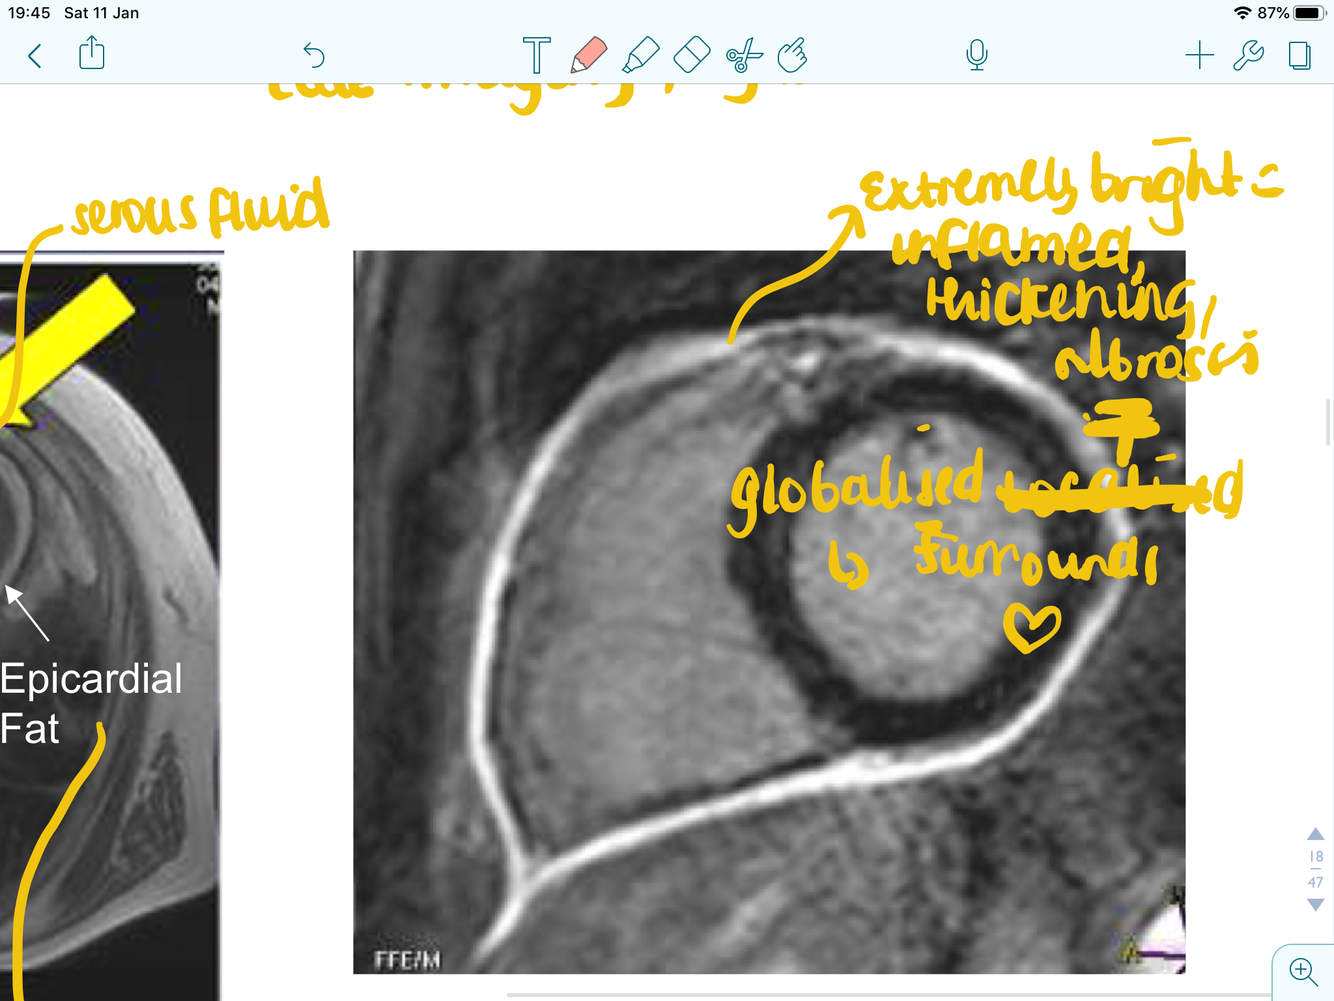

what doe this image show and what type of test is it?

MRI